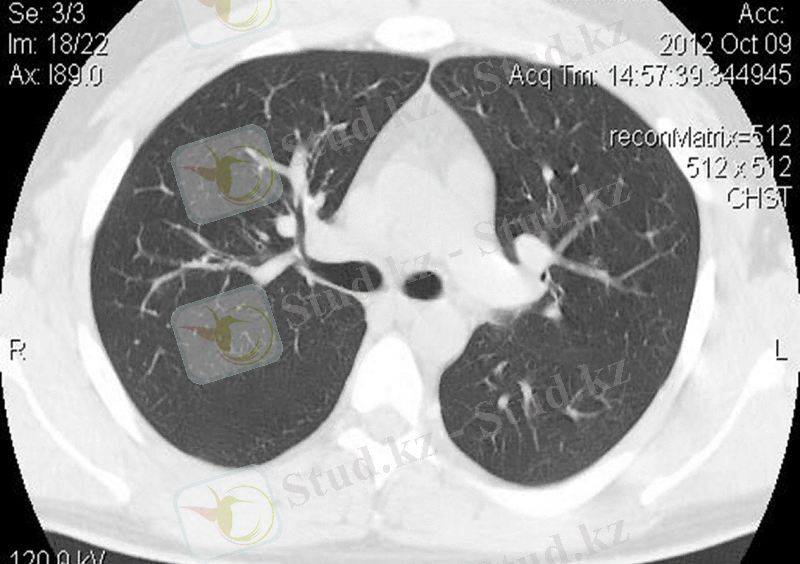

Бөлікаралық плевраның КТ суреті

КТ әр өкпедегі өкпе лобтарын бейнелей алады. Бірақ 10 мм қалыңдықтағы кесіндіде қиғаш орналасуына байланысты бөлікаралық жарықтар көрінбейді. Олардың орналасуын жанама белгілермен анықтауға болады, ені 20-30 мм кеңістіктерде үлкен тамырлар жоқ.